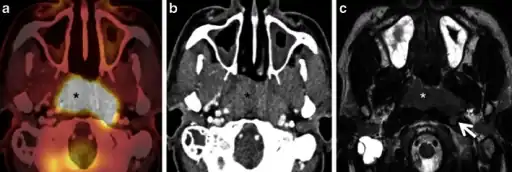

Diagnosis

Staging of nasopharyngeal carcinoma is based on clinical and radiologic examination. Most patients present with Stage III or IV disease.